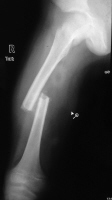

transverse fracture

spiral/ oblique fracture

Comminuted fracture